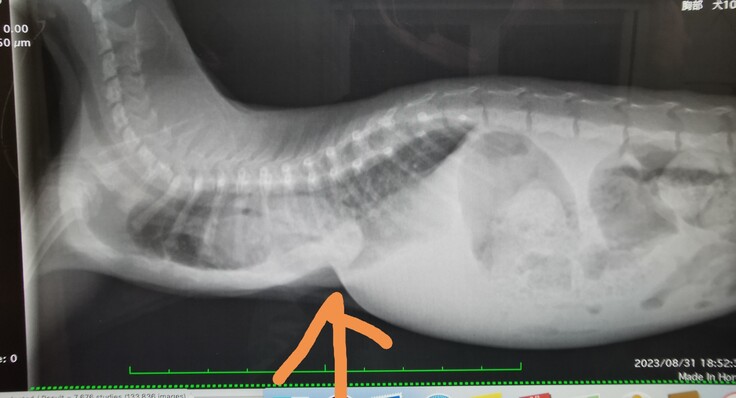

家に連れて帰ってすぐに動物病院にいったところ、肺炎と重度の漏斗胸と診断を受けました。

漏斗胸とは、胸骨が変形し陥没して心臓や肺を圧迫する先天性の疾患です。陥没した骨によって、らいむは心臓の偏位(圧迫されて通常の位置にない)気道狭窄、肺の低形成、食道狭窄を引き起こしてました。そのため呼吸困難、食欲不振による体重減少が著明でした。治療するには曲がった骨にプレートを入れて矯正する手術が必要になります。手術をしないと半年も持ちませんと主治医より言われました。

又手術時期は骨がやわらかい3か月までに行う必要があります。しかし、らいむは2か月で600gしかなく、炎症データが上昇しており、今手術をすると命を落とすと言われました。又漏斗胸の手術はまだ確立されておらず、手術をしてくれる病院は少なく、2県隣の病院に通っております。手術をするしか生きる道は残されていないため、らいむの生命力にかけたいと思います。炎症データが下がれば、すぐに手術をしたいのですが、出せるお金に限界があるため、かなり厳しいです。そこでみなさまのお力をお借りできないかと思い、このプロジェクトを立ち上げた次第です。

<診断書>

※ぺージ上の掲載している診断書、診療明細書、レシート、領収書などの資料は、動物病院、業者からの承諾を得ております。

(動物病院、獣医師名は伏せております)